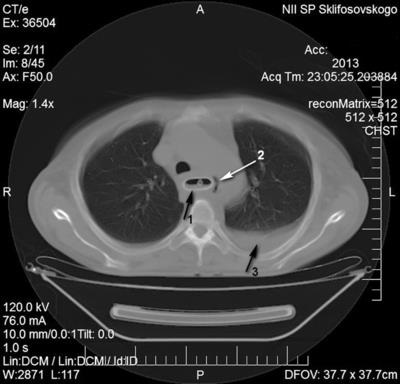

IV stádiumban nyelőcsőrák felvett betegek sürgősségi SRI utáni 7. napon endoszkópos bougienage és SP klinikai-instrumentális mediastinitis állítható képet (ábra. 1).

Kezelés Intézet Sürgősségi ellátás végrehajtása három szakaszból áll. Először is, hogy biztosítsa a megfelelő enterális táplálás készült Laparotomiát Nissen LF, gastrostomia Kader. Miután javítása tápláltsági állapota, köpölyözés aspirációs tüdőgyulladás második szakaszban végzett jobb thoracotomia, reszekció mellkasi nyelőcső, egy bal oldali kolotomiyu, megszüntetése tracheo fistula a műanyag légcső defektus izom- periosteum lebeny, traheofissuru képződik a T-alakú cső. Működés közben a stent távolítani. Miután 8 hónappal a beteg kialakított mesterséges nyelőcső a vastagbél annak retrosternalis helyét.